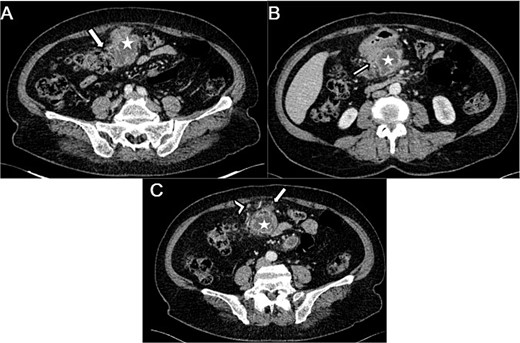

The abdominal CT scan revealed a pre-pancreatic mass occupying the greater omentum, specifically located in the mesocolon, measuring 54 × 66 × 99 mm. The mass was fairly well-defined, with irregular contours, and had a heterogeneous density. It contained liquid areas in its center and showed peripheral enhancement. This mass infiltrated the transverse colon (Fig. 1A), the head of the pancreas, and the adjacent gastric wall (Fig. 1B) with no vascular invasion. Few satellite lymph nodes were noted (Fig. 1C). Following the imaging results, a GIST or complicated duodenal diverticula was suspected.

Axial sections of an abdominal CT showing (A) a heterogenous mesocolic mass (white star) infiltrating the transverse colon (White arrow), (B) the pre-pancreatic mass (white star) infiltrating the adjacent gastric wall (white arrow), (C) the mesecolic mass (white star) with stranding of the adjacent fat (white arrow) and satellite lymph nodes (white arrow head).